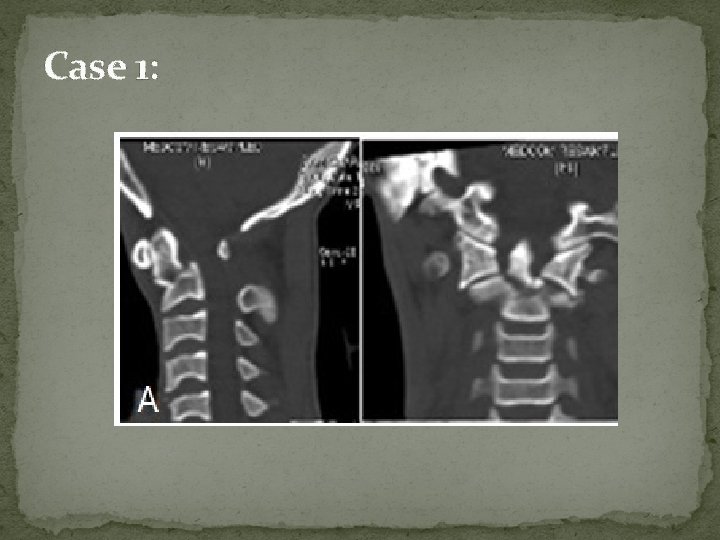

Case 1:

Post traction X-ray showing well aligned fracture

3 rd day post-operative scan showing loss of reduction with screw cut-through from C 2 body.

Reason for screw cut through Reassessment of post traction X-ray reveals to us that due to additional chip #, there was inadequate C 2 body bone available for screw to have adequate purchase